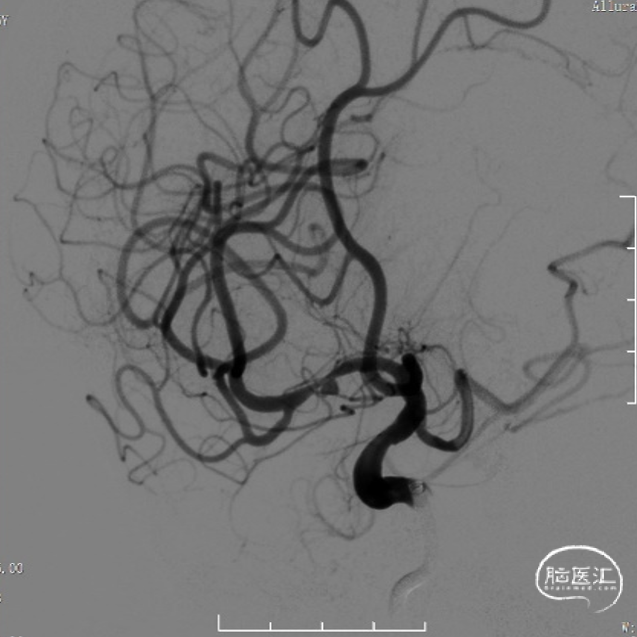

脑血管造影:右侧大脑中动脉M1段局部瘤样突起,远端重度狭窄,考虑右侧大脑中动脉M1段夹层动脉瘤。

右侧颈内动脉正侧位和右侧大脑中动脉工作位造影。

治疗之前3D和工作位(测量病变处近远端血管管径,M1近端1.9mm,M1远端1.7mm)。